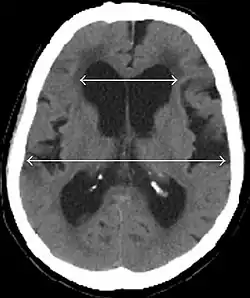

Evan's index is the ratio of maximum width of the frontal horns to the maximum width of the inner table of the cranium. An Evan's index more than 0.31 indicates hydrocephalus.[19]

• Imaging from magnetic resonance imaging (MRI) or computed tomography (CT) is needed to demonstrate enlarged ventricles and no macroscopic obstruction to cerebrospinal fluid flow. Imaging should show an enlargement to at least one of the temporal horns of lateral ventricles, and impingement against the falx cerebri resulting in a callosal angle ≤ 90° on the coronal view, showing evidence of altered brain water content, or normal active flow (which is referred to as "flow void") at the cerebral aqueduct and fourth ventricle.

Typical imaging findings in normal pressure hydrocephalus versus brain atrophy.[21]

Normal pressure hydrocephalus Brain atrophy

Preferable projection Coronal plane at the level of the posterior commissure of the brain.

Modality in this example CT MRI

CSF spaces over the convexity near the vertex (red ellipse ) Narrowed convexity ("tight convexity") as well as medial cisterns Widened vertex (red arrow) and medial cisterns (green arrow)

Callosal angle (blue V) Acute angle Obtuse angle

Most likely cause of leucoaraiosis (periventricular signal alterations, blue arrows ) Transependymal cerebrospinal fluid diapedesis Vascular encephalopathy, in this case suggested by unilateral occurrence

MRI scans are the preferred imaging. The distinction between normal and enlarged ventricular size by cerebral atrophy is difficult to ascertain. Up to 80% of cases are unrecognized and untreated due to difficulty of diagnosis.[22] Imaging should also reveal the absence of any cerebral mass lesions or any signs of obstructions. Although all patients with NPH have enlarged ventricles, not all elderly patients with enlarged ventricles have primary NPH. Cerebral atrophy can cause enlarged ventricles, as well, and is referred to as hydrocephalus ex vacuo. For these reasons it's utmost important to note that Evan's index although commonly used in imaging is not very specific for NPH. One recent systematic review and meta-analysis suggests that callosal angle has high diagnostic performance and is commonly used together with Evan's index.[23]